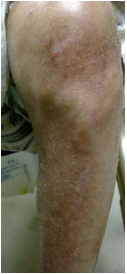

34 一位 80 歲男性,下肢出現如圖所示的搔癢脫屑病變,而這種皮膚病每到冬天都會復發,夏天就改善。 他冬天習慣用很燙的熱水浸泡患部,最可能診斷是:

(A)尋常性乾癬(psoriasis vulgaris) (B)過敏性接觸性皮膚炎(allergic contact dermatitis) (C)脂漏性皮膚炎(seborrheic dermatitis) (D)缺脂性濕疹(asteatotic eczema)